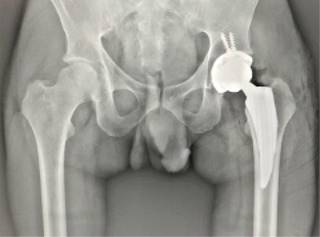

Tras los hallazgos radiográficos y la importante limitación de movilidad para el desarrollo de las actividades de la vida cotidiana, se propone y realiza recambio total de cadera izquierda mediante abordaje posterolateral. Durante el evento quirúrgico se observa de manera macroscópica la cabeza femoral, la cual muestra zonas de necrosis ósea y geodas en su interior (Figura 2). En cuanto a los componentes articulares, se utilizan componentes no cementados descritos a continuación: copa acetabular #54 (G7 Zimmer-Biomet), vástago corto #4 (Taperloc Microplasty Zimmer-Biomet), cabeza de cerámica #36 ± 0 mm y Liner 54/36 UHXLP (Figuras 3 y 4).

Figura 4: Control radiográfico posterior a realizar artroplastía total de cadera izquierda con componentes no cementados y el uso de un vástago corto.

Durante el postoperatorio cursa sin incidentes e inicia la deambulación con apoyo de andadera 12 horas posteriores a la cirugía, con disminución de dolor de cadera izquierda a 2/10 en la escala visual analógica (EVA), así como mejora importante de los arcos de movilidad.